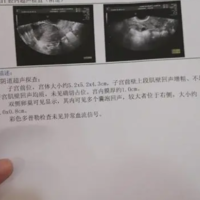

做b超监测卵巢卵泡之前需要健康饮食、注意检测时间、注意局部卫生。通过卵泡监测最能客观反映卵泡生长发育状况,观察是否有排卵,并同步反映子宫内膜的发育状况。在做卵泡监测前需要注意局部卫生,保持局部卫生的情节,还要保持良好的生活习惯,包括健康饮食、充足睡眠和适量运动,以确保身体处于最佳状态,还要注意监测时间,月经规律和不规律的女性监测时间不同。监测卵泡这种检查看起来比较麻烦,但非常重要,具有重要的临床意

大姨妈走后10天左右是b超查卵泡的最佳监测时间。一般情况下,女性月经周期是30天左右,通常在下次月经开始前的14天进行排卵。而查卵泡最好是在卵泡生长的早期阶段进行监测,这样可以帮助确定卵泡的数量、大小和生长情况,为后续的生育或者健康状况提供重要的信息。卵泡监测是女性生殖内分泌科常见的一种检查,可以通过B超进行监测,能够观察到卵泡的发育情况。而卵泡的发育是随着月经的周期而变化的,一般的在下次月经前1

监测发现卵泡21x14mm形态并不能说明太扁成熟度不好。卵泡扁并不代表质量成熟度不好,扁形的卵泡也属于正常卵泡,正常的卵泡发育是圆形或者椭圆形,决定卵泡质量的好坏,主要是排出的卵子质量,对于卵泡是扁或圆关系不是太大,绝大部分的卵泡都是椭圆形,并没有绝对那么圆,如果卵泡接近于圆形,张力越大,排出卵子的可能性也就越大。卵泡多大才算成熟是根据个人的体质来决定的,每个人的情况都不太一样的,一般来说,正常的

对于备孕中的女性来说,掌握排卵期是一个非常重要的事情,毕竟在排卵期前后同房怀孕的几率才会比较高。科学备孕是要求女性要多加关注自己的排卵情况,可以在家用排卵试纸也可以到医院进行b超检查。一般来说, 卵泡大小与内膜厚度是有一定对照的,不同时期子宫内膜厚度和卵泡大小都有一定区别,所以要想一次达到怀孕就需要多加关注这两者之间的关系。卵泡大小与内膜厚度对照表分析正常情况下,子宫内膜厚度在5-10mm左右。子

女性在平时的生活中如果不注意保养身体就很容易出现卵巢异常的情况,这种情况就会影响到女性的受孕成功率。所以有些不孕的女性会进行卵泡监测,卵泡监测可以了解清楚卵泡的生长发育。那么卵泡监测从什么时候开始?卵泡监测从什么时候开始?查卵泡配塌的时间是从月经来潮的第1天开始一直到第11天的时候。目前监测卵泡的方法主要是通过阴道彩超进行,阴道彩超的优势在于无需喝水憋尿,如果监测时没有发现优势卵泡,可间隔1到2天

卵泡监测是监测女性卵泡发育情况的的一种手段,用于确定卵子是否已经成熟,是否适合进行人工受孕或者性行为。那什么时候做卵泡监测好?测卵泡什么时候测最准大多数女性朋友为了能够顺利怀孕,都是会进行卵泡监测的,而因为对于这方面知识的欠缺,所以并不清楚自己应该在什么时候去进行卵泡监测才能得到最准确的结果,那么你知道什么时槐信候测卵泡最准吗?下面我们就来看看问题的答案吧。卵泡发育从月经第一天开始,进入卵泡期,逐

很多人为了顺利怀上宝宝,会积极备孕,那么其中测排卵期就是一个很好的办法,如果能更准确地判断出排卵期,那么受孕的几率就会更大。那你知道测排卵期什么时间测最准吗?早上还是晚上。b超测排卵的最佳时间一般针对月经周期规律的人群来说,测排卵的最佳时间是在月经期的结束之后的第二到三天开始进行监测。以后每一天监测一次,在下一次月经之前的第十四天,一般为排卵的日期。在这之前应该每天进行排卵的检查,正常的卵泡应该是